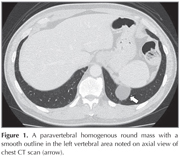

A 59-year-old man with no symptom was referred for a paravertebral homogenous round mass with a smooth outline in the left vertebral area incidentally noted on axial view of chest computed tomography (CT) scan (Figure 1). He had no medical history. The coronal and sagittal images of chest CT scan revealed continuity of the soft tissue line of the left diaphragm adjacent to the mass and protrusion of retroperitoneal fat into the thoracic cavity through diaphragmatic defect (Figure 2). Therefore, the patient was diagnosed to have Bochdalek hernia. As the patient had no symptom and benign nature of the disease, surgical resection was not performed.

Figure 1